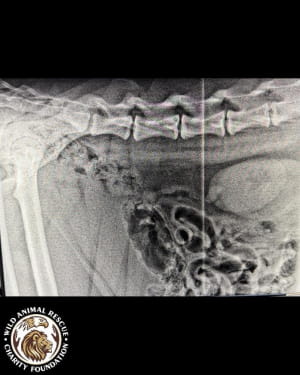

Тварині лише рік, але вона вже стала глибоким інвалідом. Тигриця не здатна самостійно підвестися і ледве пересувається, спираючись виключно на передні лапи. Після ретельного обстеження ветеринари були шоковані станом кісток молодого хижака.

• Критична атрофія м’язів та рахіт.

• Дегенеративні зміни у хребетному стовпі.

• Загальна деформація кісток скелета.

• Двобічна дисплазія кульшових суглобів.

• Остеоартроз та патологічне ремоделювання головки стегнової кістки.